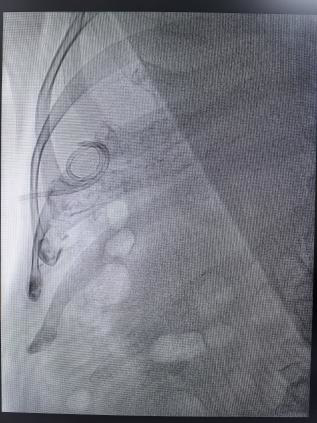

在彩超实时定位+DSA血管造影双精准引导下,介入医生梁炳钊仅用15分钟便完成穿刺操作,一次性引出60ml黄绿色脓性液体,反复用生理盐水冲洗胆囊腔后,患者原本紧绷的腹部逐渐放松,直呼“不疼了”,术后监测血压、心率均恢复平稳。